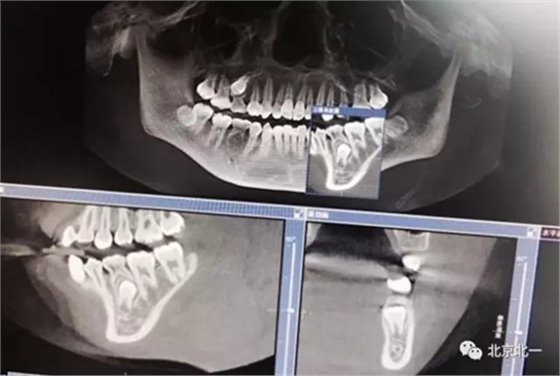

圖一:拔牙前影像片(CBCT)